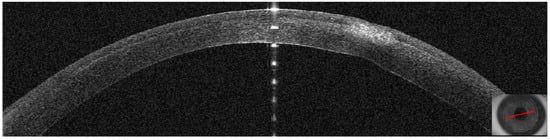

3.1. Patient #1